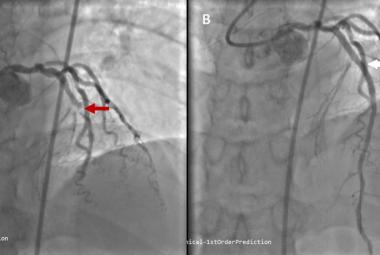

Unilateral Pulsatile Tinnitus in Young Female Adults: A Report of Two Cases

Early Recognition and Intervention of De Winter Syndrome: A Case Report